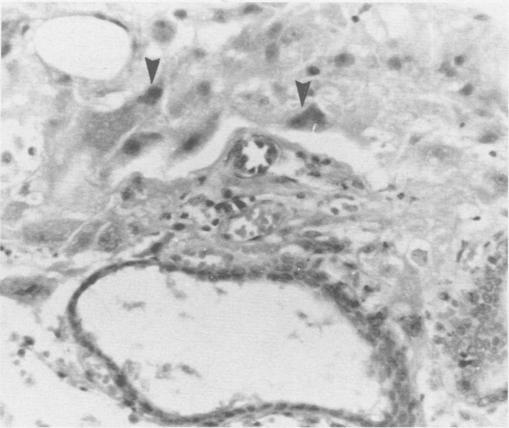

Ninety-eight reproductive tracts from dogs at different postpartum time periods were used to investigate stages of normal involution. Seventy-eight reproductive tracts were obtained from the field, and 20 obtained surgically for gross and microscopic examination. Plasma progesterone was measured in 22 dogs at various times postpartum. The uterine horns during the first week postpartum were dilated and edematous. The placental sites were 1.5-3 cm in width, rough, granular and covered with mucus and a few blood clots. By the fourth week the placental sites were thick, grayish-tan and nodular with a few blood clots within nodules. The uterine horns during the seventh week were greatly contracted and the placental sites were narrow and light in color. A few nodules were still present on the surface. By the ninth week the uterine horns were uniform in shape and contracted with a narrow lumen. The placental sites appeared as a narrow brown band. Histologically the placental sites during the first week postpartum were covered by an eosinophilic staining necrotic mass and a few intact epithelial cells scattered on the surface as an interrupted single layer. Under the necrotic mass, large eosinophilic staining cells in moderate number were scattered throughout the lamina propria of the placental site. These cells were considered to be decidual cells. By the fourth week the placental sites were covered by a large lobulated mass of collagen fibers. The uterine glands were greatly dilated and degenerate, and mononuclear cell infiltration in the lamina propria was pronounced. By the seventh week, large masses of collagen fibers were detached from the surface, and endometrial glands were normal in size and shape. By the ninth week surface sloughing was completed. However, regeneration and replacement of the endometrial lining from the mouth of the uterine glands continued until the end of the twelfth week when the involution process was completed. The progesterone levels were very low for eight weeks postpartum.

98条处于不同产后时期的犬生殖道用于研究正常 involution 的阶段。78条生殖道取自野外,20条通过手术获取用于大体和显微镜检查。在产后不同时间对22只犬测量血浆孕酮。产后第一周子宫角扩张且水肿。胎盘部位宽1.5 - 3厘米,粗糙、呈颗粒状,覆盖有黏液和少量血凝块。到第四周时,胎盘部位增厚,呈灰棕色且有结节,结节内有少量血凝块。第七周时子宫角大幅收缩,胎盘部位变窄且颜色变浅。表面仍有一些结节。到第九周时,子宫角形状均匀且收缩,管腔狭窄。胎盘部位呈现为一条狭窄的棕色带。组织学上,产后第一周的胎盘部位被嗜酸性染色的坏死物质覆盖,表面有一些完整的上皮细胞散在分布,形成间断的单层。在坏死物质下方,中等数量的大嗜酸性染色细胞散在分布于胎盘部位的固有层。这些细胞被认为是蜕膜细胞。到第四周时,胎盘部位被大量分叶状的胶原纤维团覆盖。子宫腺大幅扩张并退化,固有层单核细胞浸润明显。到第七周时,大量胶原纤维从表面脱落,子宫内膜腺大小和形状正常。到第九周时表面脱落完成。然而,从子宫腺开口处开始的子宫内膜衬里的再生和替代持续到第十二周结束时 involution 过程完成。产后八周孕酮水平非常低。